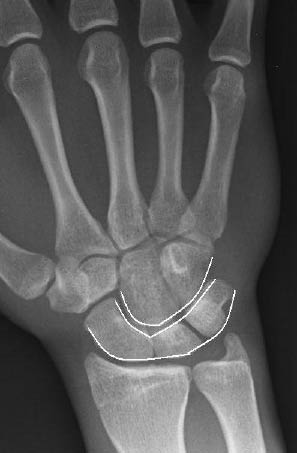

Figure 6: Radiographic Lines on the Carpal Bones Described by Gilula

PA radiograph with radiographic lines described by Gilula for carpal bone alignment. Disruption of any of these lines may represent carpal bone instability or other possible injury.32

The diagnostic imaging includes standard PA and lateral radiographs. When reviewing these plain radiographs, one should pay close attention to the space between the individual carpal bones on the PA view. The space between the bones should be uniform. The presence of a gap greater than 2 mm is indicative of ligamentous injury and possible carpal instability.32 Gilula described radiographic lines for discovering carpal bone injuries due to ligamentous and bony injuries of the wrist.33 In an uninjured wrist, the articular surfaces of the proximal and distal carpal rows form smooth arcs at the radiocarpal and midcarpal articulations.32 (See Figure 6.) A disruption of any of these lines is indicative of carpal instability or possible injury.32 The lateral view of the wrist is often the best view to appreciate a perilunate dislocation. Remember the "3 Cs" sign when examining a lateral radiograph of the wrist. The "3 Cs" are formed by the articulations of the distal radius, lunate, capitate, and base of the third metacarpal, respectively. (See Figures 7 and 8.) The arrangement of the 3 Cs in a perilunate dislocation is disrupted at the level of the capitate, which represents the third C. It is displaced dorsally toward the lunate, which remains in contact with the radius.12 (See Figure 9.)